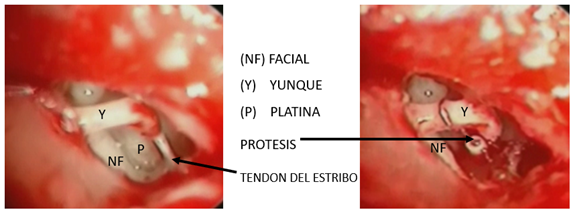

Presente en el 0,6 al 6% de los pacientes. Cuando se presenta, se realiza una resección de la cabeza y se aplica una prótesis que va desde el mango del martillo a la platina, lo que se le conoce como maleoestapedectomía (Fig.12-13).

La técnica clásica de estapedectomía consiste en una vez visualizado el estribo, el yunque, la apófisis piramidal, la ventana oval y redonda; cortar el tendón del estribo, retirar la superestructura del estribo, realizar la fenestración y, finalmente, colocar la prótesis.